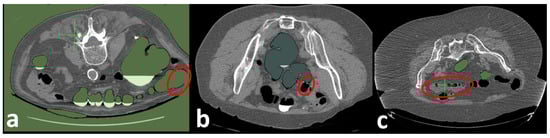

Figure 9.

Examples of bad scans that need manual annotations: (a) Patient is not accurately positioned, (b) thickened colonic folds, and imaging artifacts and distortion due to low-dose CT.,(c) patient is not good prepped (colon is not empty).